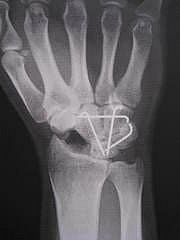

二日ぶりのコンニチワです。 20日水曜日に予定どうりにオペに挑みました。 病室からオペ室まで看護師さんと話をしながら歩いていきました。 周りから見るとどこが悪いの??って思われそうです(笑) 手術は何度もありますが全身麻酔は始めての経験なので 多少の不安はありましたが・・ありゃ凄い...